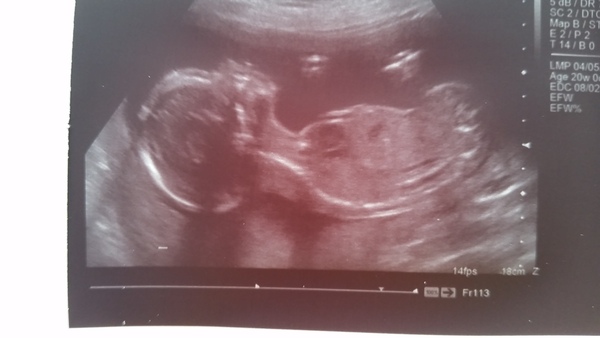

feel a bit naughty that I didn't stick a pic up! We only had this one as most of the other views were wriggling.